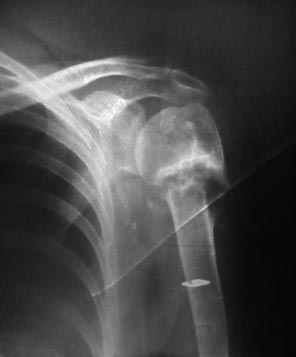

Здесь рентгенологическая картина несращения. При переломах срок без клинико-рентгенологической картины о чем-то определенном говорит только ранний. В 2,5 мес. может быть уже прочно сросшийся перелом, а может быть болтающаяся подвижность. То есть с момента травмы процесс может идти в сторону несращения. Что мы здесь и видим.

Аппарат для управления положением отломков тут пригодится.Для окончательной фиксации PHN - самое то. Между отломками мы видим диастаз. С признаками "неэффективного" костеообразования. На центральное отломке даже склероз по линии перелома.

Денис, а Вы сформированные замыкательные пластинки на Ртг правда не видете? Оно конечно, prima clinica, sekunda retgenologica, но рентгенологическое признаки ложного сустава налицо.

По снимку все видно - несращение формируется. Плюс есть варусная деформация, которую стоит устранить, даже если бы срослось.

Варус тут 15 градусов. Будет дефицит отведения, подакромиальный импинджмент... А снимки надо делать, да, и две проекции (предплечье на животе - предплечье вперед), и аксиальный, а для выявления подвижности - с максимальным отведением...

Да еще одно скажу, как все заменили на дистальном конце головки явный склероз, пока его не удалить сращения мы не получим